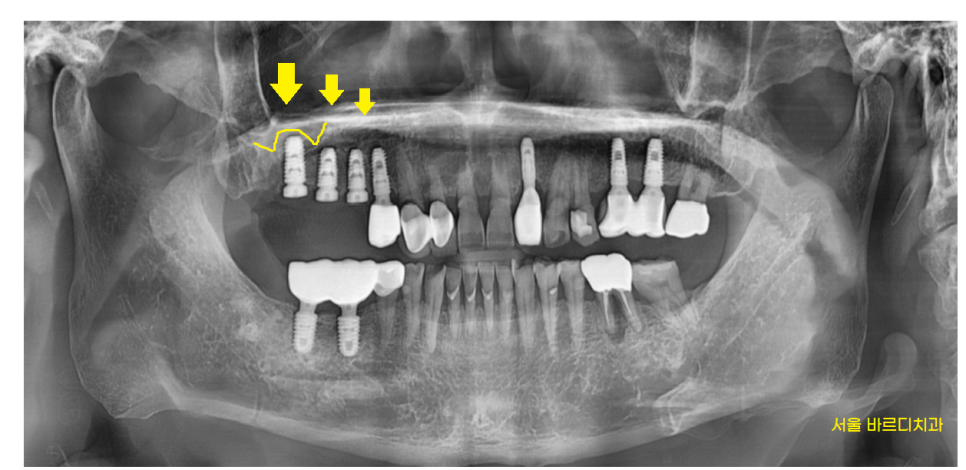

x-ray 를 우선 찍어보니

충치가 먹은게 보였습니다.

230313

요즘은 잘 쓰지 않는

은색 치아인걸보니

치아를 씌운지 정말 오래되셨나봅니다.

당일 문제 치아 발치 후 상악동 거상술을 동반한 뼈이식

진행하였는데요.